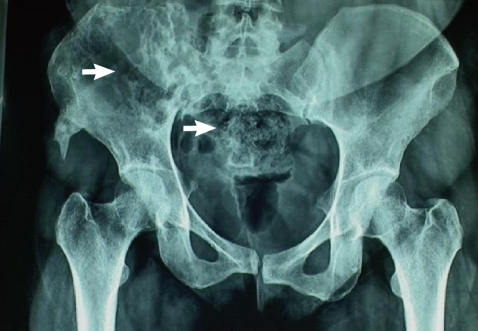

The patient continued with the pelvic pain although postoperative MRI showed reduction in size of the lesion along the right iliac bone and sacroiliac joint. No new lesion was, however, seen. The x-ray of the pelvis and hips revealed cortical irregularity with ill defined lytic defects and linear areas of patchy sclerosis along the right iliac blade (Fig. 1). She continued with pain and follow-up CT reviewed after 8 months revealed extension of the disease. The patient was then referred to our hospital. On physical examination, local tenderness was present on the back of the right limb and hip. The range of motion of the right hip was painful and restricted. No distal neurovascular deficits were present. Blood investigations were within normal range. Surgery was planned for removal of the residual disease. The preoperative MRI and CT showed progression of the disease. The CT showed a multiloculated cystic lesion (Fig. 2) involving the medullary cavity of the right iliac bone resulting in irregular lytic destruction and extending across the right sacroiliac joint into the right half of the sacrum, right sacral foramina, and adjacent soft tissues. Resection of the hydatid cyst of sacroiliac region with allograft and autograft (rib graft) with lumbosacroiliac fixation was done.